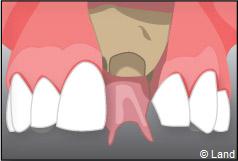

Le chirurgien-dentiste après une anesthésie locale pratique une incision, puis il décolle la gencive pour accéder à l’os alvéolaire.

Ensuite il prépare l’emplacement de l’implant dans l’os en passant plusieurs forets de diamètre croissant. Le forage de l’os se fait à vitesse maîtrisée et lente sous irrigation, pour respecter la structure osseuse et éviter tout échauffement de celle-ci. Le praticien arrête lorsqu’il a obtenu un puits d’un diamètre très légèrement inférieur à l’implant à poser.

L’implant est placé dans l’os le plus souvent par vissage et doit avoir une liaison forte avec l’os. Le praticien replace alors la gencive et pose des points de suture.